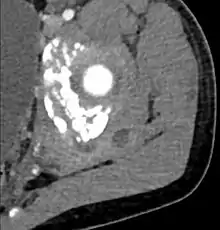

| Diagnostic method | Diagnostic method used for PM includes ultrasound, CT scan and MRI. Ultrasound can be helpful in showing muscular heterogeneity or a purulent collection but it is not useful during the first stage of the disease. CT scan can confirm the diagnosis before abscesses occur with enlargement of the involved muscles and hypodensity when abscess is present, terogenous attenuation and fluid collection with rim enhancement can be found. MRI is useful to assess PM and determine its localization and extension |